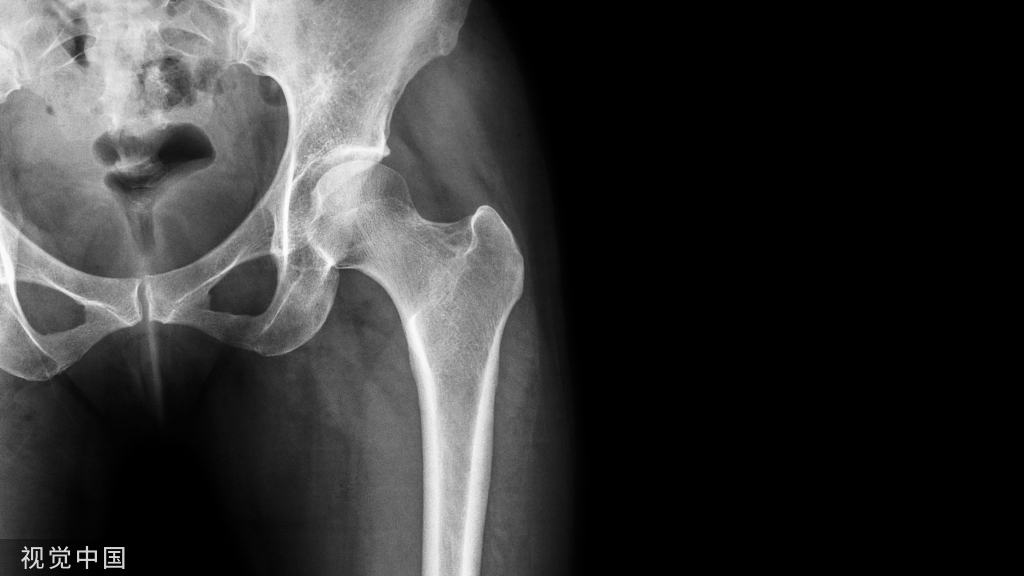

疼痛是骨科患者的重要主诉之一,根据持续时间不同分为急性疼痛和慢性疼痛。急性疼痛通常与骨骼肌肉系统、神经系统的外力或其他损伤相关,如术后疼痛或创伤性疼痛、感染源性疼痛等。骨科手术治疗或运动系统创伤所造成的急性疼痛,发生率近乎100%,因损伤程度和个体感受的差异,疼痛程度存在个体差异。规范化的疼痛管理可以在提高医疗质量的同时达到节约医疗成本的效果。当前国内外虽有多个骨科疼痛相关指南或共识,还存在以下局限:①国内外骨科医生对疼痛的认识度不同;②国内外骨科医生临床实践环境不同;③国内外医生对不同种类镇痛药物的使用经验和了解程度不同;④国内不同地区医疗保险药品收录内容不同;⑤国内疼痛相关指南的方法学和报告质量低于国际水平,多未结合国内医疗体系以及医疗保险药品目录,多未采用国际通用指南制订方法。

慢性继发性骨骼肌肉痛的特点是随着疾病进展,其疼痛程度会越来越重,持续时间越来越长;疼痛性质为伤害感受性疼痛或混合性疼痛。患者多为老年人,合并症多,肝肾功能储备下降。当前尚无明确干预措施能延缓骨骼肌肉系统退行性病变的进展和改善患者功能,疼痛控制效果是进行慢性疼痛管理的本质需求。